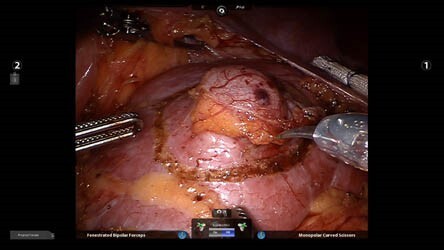

Ρομποτική Νεφρεκτομή

Ο καρκίνος του νεφρού μπορεί να τύχει ίασης, η οποία κατορθώνεται σχεδόν αποκλειστικά από τη ριζική χειρουργική εξαίρεσή του (ο νεφρός και ο όγκος του με όλο το περινεφρικό λίπος). Η ριζική αφαίρεσή του μέσω του ρομποτικού συστήματος DaVinci (ρομποτική νεφρεκτομή), απαιτεί ιδιαίτερη εμπειρία και λεπτότατους χειρισμούς.

Για τους παραπάνω λόγους, αλλά και εξαιτίας του γεγονότος πως ο νεφρός βρίσκεται πλησίον μεγάλων αγγείων (αορτή, κάτω κοίλη φλέβα), αποτελεί αντικείμενο ιδιαίτερης εκπαίδευσης και αποκτηθείσας εμπειρίας με άριστα αποτελέσματα, όσον αφορά στην επιβίωση των ασθενών με εντοπισμένο καρκίνο του νεφρού.

Και στις 2 επεμβάσεις (ρομποτική νεφρεκτομή και ρομποτική νεφροουρητηρεκτομή) η έξοδος από το νοσοκομείο πραγματοποιείται 2 ημέρες μετά την επέμβαση, ενώ η πιθανότητα μετάγγισης τέτοιων ασθενών σχεδόν είναι παρελθόν με αυτή την τεχνική. Καθότι δεν υπάρχει τομή σε αυτό το χειρουργείο, το οποίο πραγματοποιείται μέσω οπών, δεν υφίσταται μετεγχειρητικός πόνος και η επάνοδος στις καθημερινές δραστηριότητες είναι εξαιρετικά ταχεία.

Η τρισδιάστατη άποψη του χειρουργικού πεδίου, η σταθερότητα και ακρίβεια των ρομποτικών βραχιόνων και οι πολλαπλοί άξονες κινήσεων προσφέρουν τα μέγιστα γι’ αυτή τη συγκεκριμένη επέμβαση, το δε κόστος έχει ελαττωθεί προσφέροντας πολύ λογικά οικονομικά πακέτα νοσηλείων.

Ρομποτική Μερική Νεφρεκτομή

Η ρομποτική μερική νεφρεκτομή πραγματοποιείται διεθνώς σε μικρούς σχετικά όγκους (μέχρι 4 εκατ.) και μακριά από τα αγγεία του νεφρού. Η αφαίρεση μεγαλύτερων όγκων (μέχρι και 6,5 εκατοστά) και κοντά στα μεγάλα αγγεία απαιτεί απόλυτη εμπειρία, συντονισμό μεταξύ των μελών της ομάδας, συγχρονισμό αποφασιστικών χειρουργικών κινήσεων και ταχύτητας, και εξαιρετικά εκπαιδευμένο αναισθησιολογικό team, ώστε να μην ισχαιμίσει ο νεφρός.

Επίσης, σε περίπτωση συνδρόμου πολλαπλών όγκων και στους 2 νεφρούς πάση θυσία θα πρέπει να διατηρούνται οι νεφροί, ώστε ο ασθενής να μην υποβάλλεται σε ακρωτηριαστικά χειρουργεία ολικής αφαίρεσης νεφρού και να παραμείνει ΆΝΕΦΡΟΣ! Έτσι, στον ασθενή αυτόν πραγματοποιείται ρομποτική μερική νεφρεκτομή και ο ασθενής αυτός διατηρεί τους νεφρούς του, ενώ και το επίπεδο διαβίωσής του εξαιρετικό, καθώς και η ελπίδα του για λαμπρό μέλλον υπαρκτή με ποιότητα ζωής. Η χειρουργική αυτή αποτελεί δείγμα εξελιγμένου και προοδευτικού ρομποτικού ουρολογικού χειρουργικού επιτεύγματος!